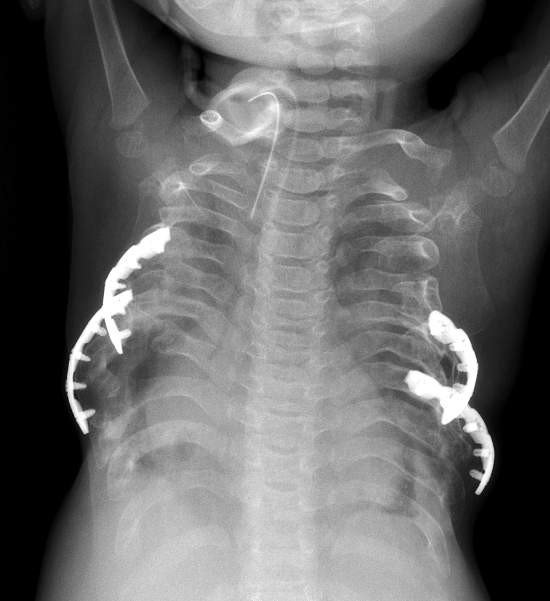

Uz. Dr. Emre Divarcı, “Jeune Sendromu (asfiktik torasik distrofi) göğüs kafesinin ciddi darlığı ile giden doğumsal bir hastalıktır. Göğüs kafesi darlığı nedeni ile akciğerler genişleyememekte ve soluk almakta ciddi sıkıntı yaratmaktadır. Solunum cihazında yüksek basınçlar gerektirmekte ve yoğun bakımdan evine gönderilememektedir. Hastaların yüzde 90’ı ilk 1 yaş içinde ciddi solunum yetmezliği nedeniyle kaybedilmektedir. Bizim hastamız da bu şikayetlerle kliniğimize yönlendirildi. Daha önce tek kardeşi yine bu hastalık nedeniyle üç aylıkken kaybedilmişti. Hastaya iki seansta her iki tarafına olmak üzere göğüs kafesini genişleten cerrahi operasyon (lateral torasik ekspansiyon) uygulandı. Operasyonda göğüs kafesinde darlığa neden olan kaburgaların altı tanesi uygun açılarda kesilip genişleme elde edilecek şekilde titanyum plaklar ile tespitlendi. Bu operasyon ülkemizde sayılı merkezlerde yapılabildiği için çoğu hasta bebeklik döneminde kaybedilmektedir. Bizim hastamızda da birer ay arayla yapılan iki operasyon sonucu solunum basınçları düşürülerek öncelikle yoğun bakımdan eve taburcu olması sağlanmıştır. Ameliyattan sonra geçen 3 yıl içinde solunum makinesi desteği giderek azalmış sadece geceleri önlem amaçlı solunum makinesi desteği gerekli kalmıştır. Yürümeye ve konuşmaya başlayan hastanın gelişimi devam etmektedir” dedi.

Jeune sendromu’nun her 70-150 bin canlı doğumda bir görüldüğünü ifade eden Uz. Dr. Emre Divarcı, “Ülkemizde her yıl yaklaşık 10- 15 Jeune Sendromlu çocuk doğmaktadır. Ege Üniversitesi Tıp Fakültesi Çocuk Cerrahisi Kliniği’nde bu ameliyatın başarı ile yapılması ülkemizdeki diğer çocuk yoğun bakım ünitelerinde yatan Jeune sendromlu çocuk ve ailelere umut oldu. Bu yaptığımız ameliyat 2016 yılı Avrupa Çocuk Cerrahisi Kongresi’nde "En İyi İkinci Olgu Sunumu Ödülü" kazanmaya hak kazandı” dedi.